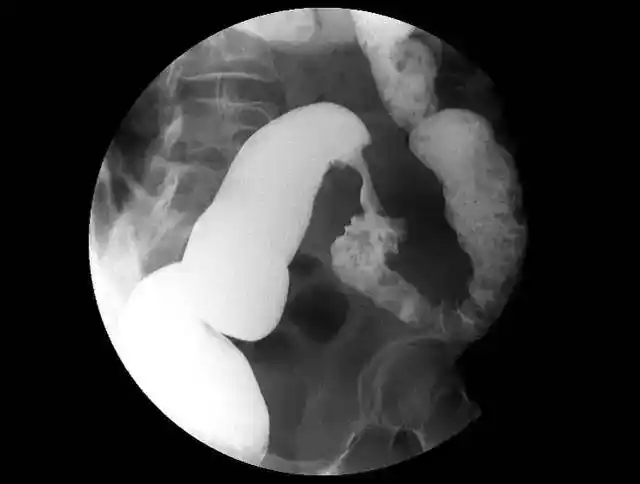

a图为鸟嘴征,b图为乙状结肠样改变

【典型"鸟嘴"征】贲门失驰缓症

征象丨多脏器之"鸟嘴征"_乙状结肠